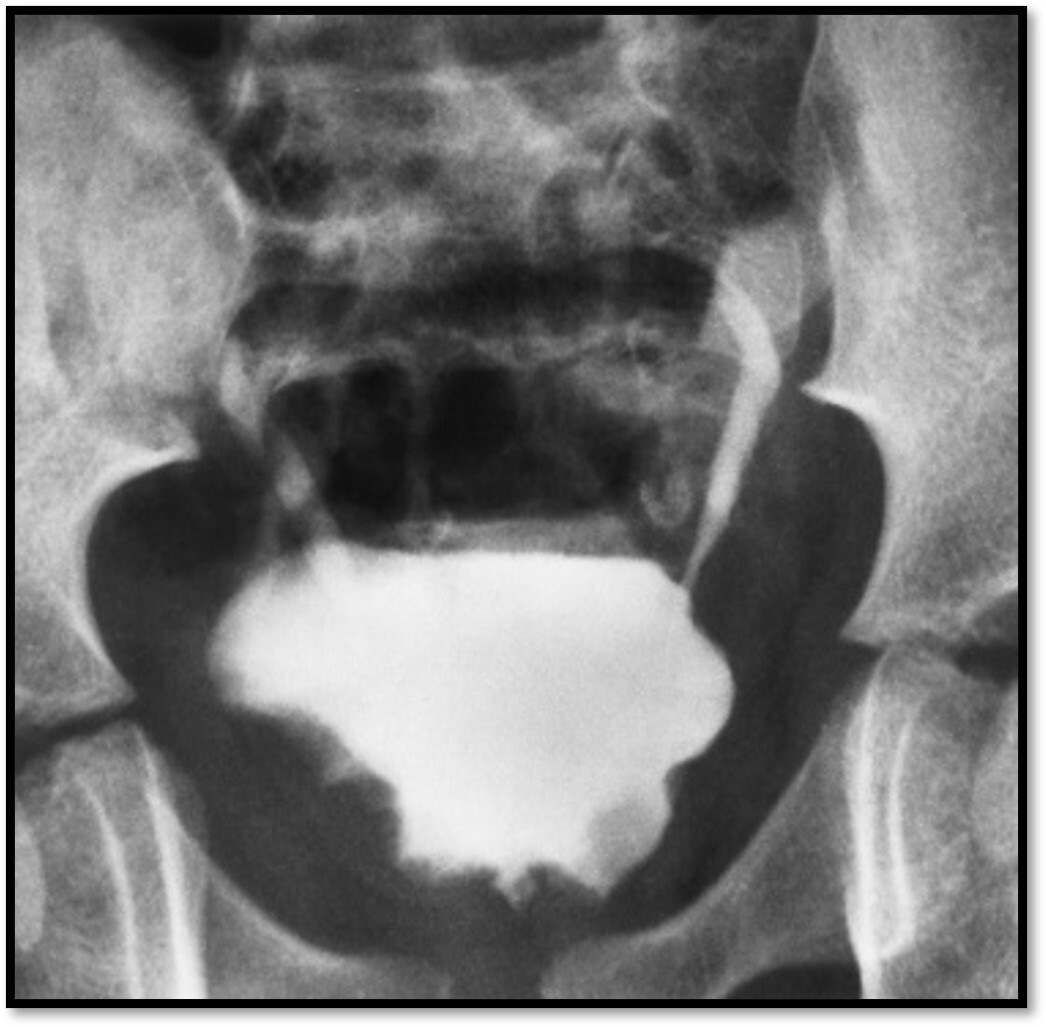

What pathology is seen here?

Prostatic Hyperplasia

45

46